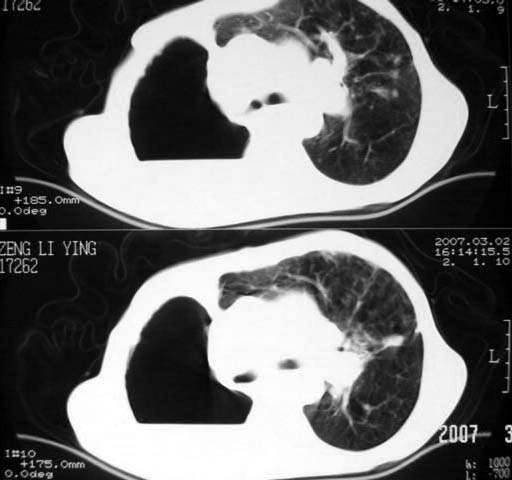

以下是引用dyqct在2007-3-2 22:04:00的发言:[br]考虑:1、右侧毁损肺伴支气管胸膜瘘(多条支气管与胸腔相通、液气胸);[br] 2、左肺浸润型肺结核。[br][br][br][br]